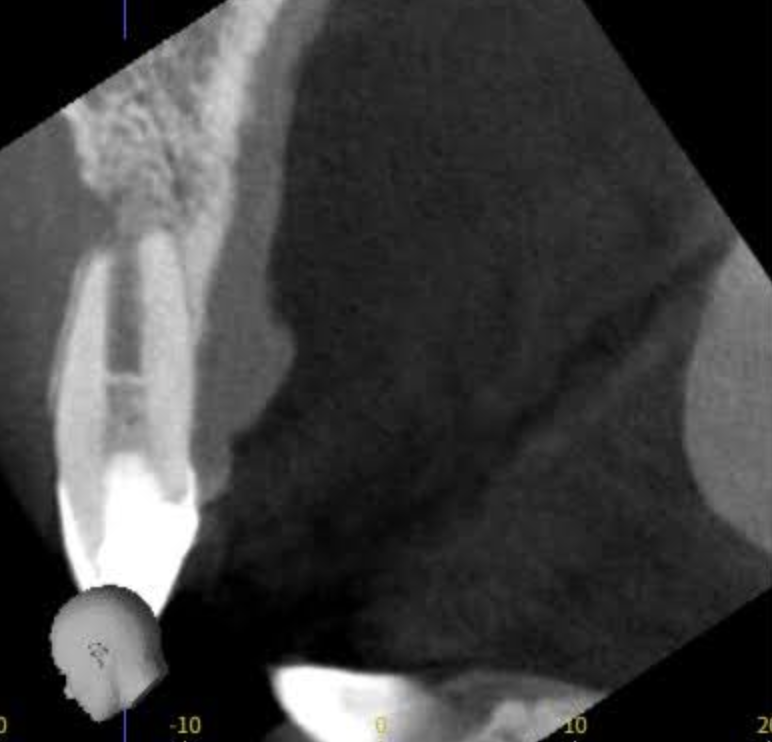

この画像は根尖病変が上顎洞まで波及し、レントゲン上に上顎洞が白い影ができて歯性上顎洞炎になっているものです。

レントゲンやCTを用いて、膿の位置・広がり・骨の状態を正確に把握します。